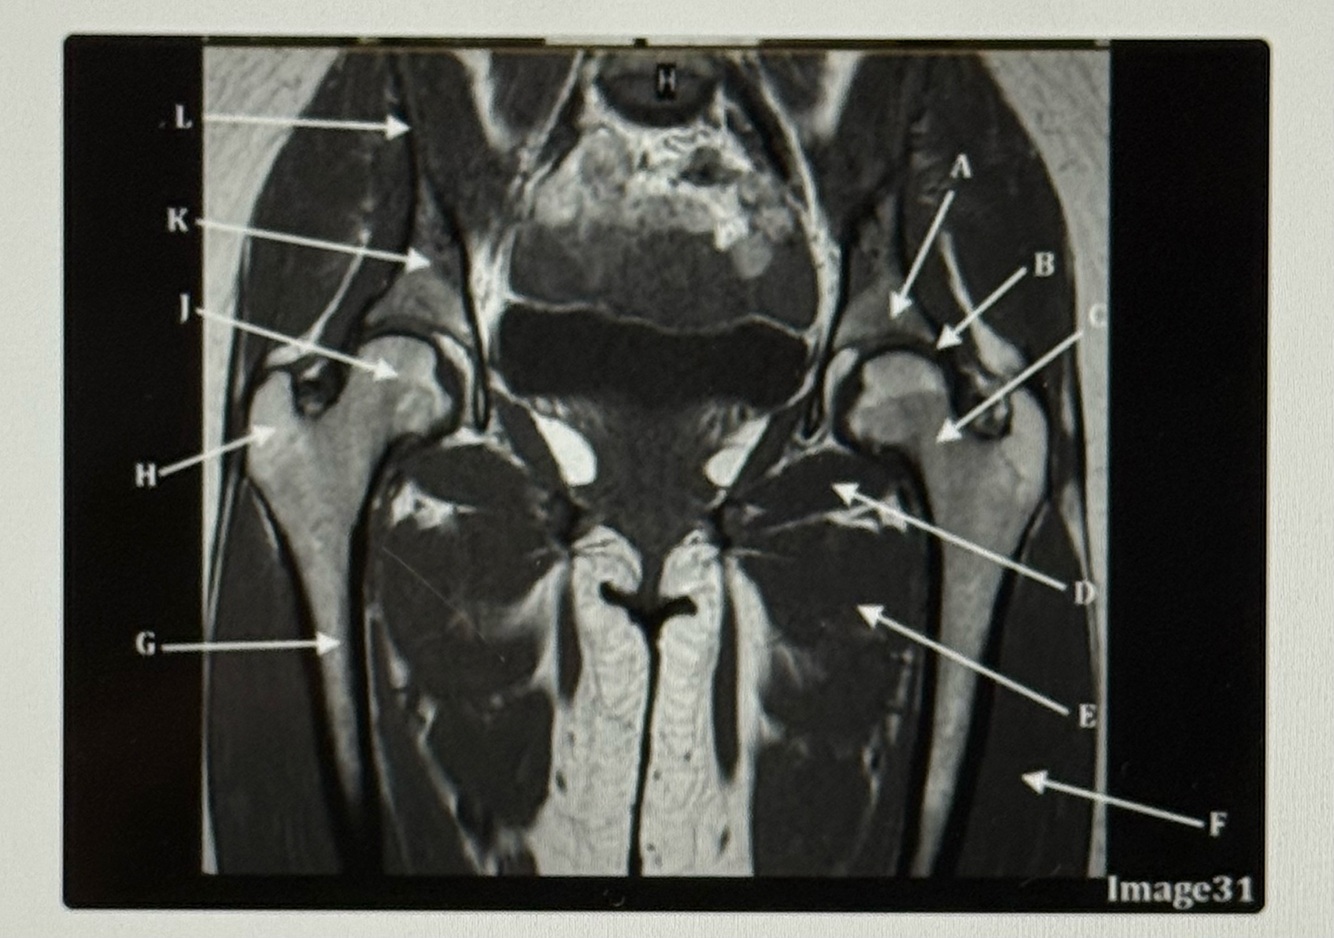

Letter A points to the

A

Acetabulum

Q

Letter B points to the

Labrum

9

Letter C points to the

Femoral neck

10

Letter D points to the

Obturator externus

11

Letter E points to the

Adductor muscles

12

Letter F points to the

Vastus lateralis

13

Letter G points to the

Femur

14

Letter H is pointing to the

Greater trochanter

15

Letter J points to the

Femoral head

16

Letter K points to the

Body of the ilium

17

Letter L points to the